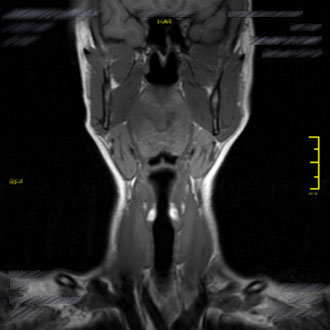

Die MRT Hals ist eine besonders wichtige Untersuchung in der Kopf-Hals-Diagnostik. Im Kernspin Zentrum Köln wird sie eingesetzt, um die Strukturen des Kehlkopfs, der Speicheldrüsen, der Lymphknoten sowie den Nasen-, Mund- und Rachenraum detailliert darzustellen.

Dank moderner Magnetresonanztomographie (MRT) lassen sich Entzündungen, Tumoren oder funktionelle Veränderungen frühzeitig und strahlungsfrei erkennen.

Die MRT der Speicheldrüsen (Parotis-, Submandibular- und Sublingualdrüsen) ist eine schmerzfreie und präzise Methode, um Veränderungen oder Entzündungen in diesem sensiblen Bereich zu erkennen.

Durch die MRT lassen sich auch kleinste Läsionen oder entzündliche Prozesse ohne Strahlenbelastung zuverlässig darstellen.

Die MRT des Nasen-, Mund- und Rachenraums (Nasopharynx, Oropharynx, Hypopharynx) spielt eine zentrale Rolle bei der Diagnose von Karzinomen, Entzündungen oder Lymphknotenveränderungen im Halsbereich.

Im Kernspin Zentrum Köln wird diese Untersuchung eingesetzt, um unklare Schluckbeschwerden, chronische Infektionen oder Raumforderungen abzuklären. Besonders bei Lymphknotenvergrößerungen kann die MRT helfen, zwischen entzündlichen und tumorbedingten Veränderungen zu unterscheiden.

Die MRT Hals im Kernspin Zentrum Köln ermöglicht eine exakte und umfassende Diagnostik sämtlicher Strukturen im Halsbereich – vom Kehlkopf über die Speicheldrüsen bis hin zum Rachenraum. Sie bietet die beste Grundlage, um Ursachen von Heiserkeit, Schluckbeschwerden, Schwellungen oder Entzündungen sicher zu erkennen und gezielt zu behandeln.